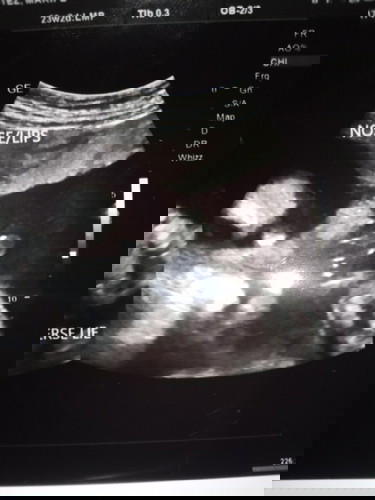

asa po diyan ung nose /lips??

pabasa mo nalang mamsh kay ob hirap rin ako sa ganyan di ko magets haha mas iniintindi ko yung result kung may prob si bb o wala